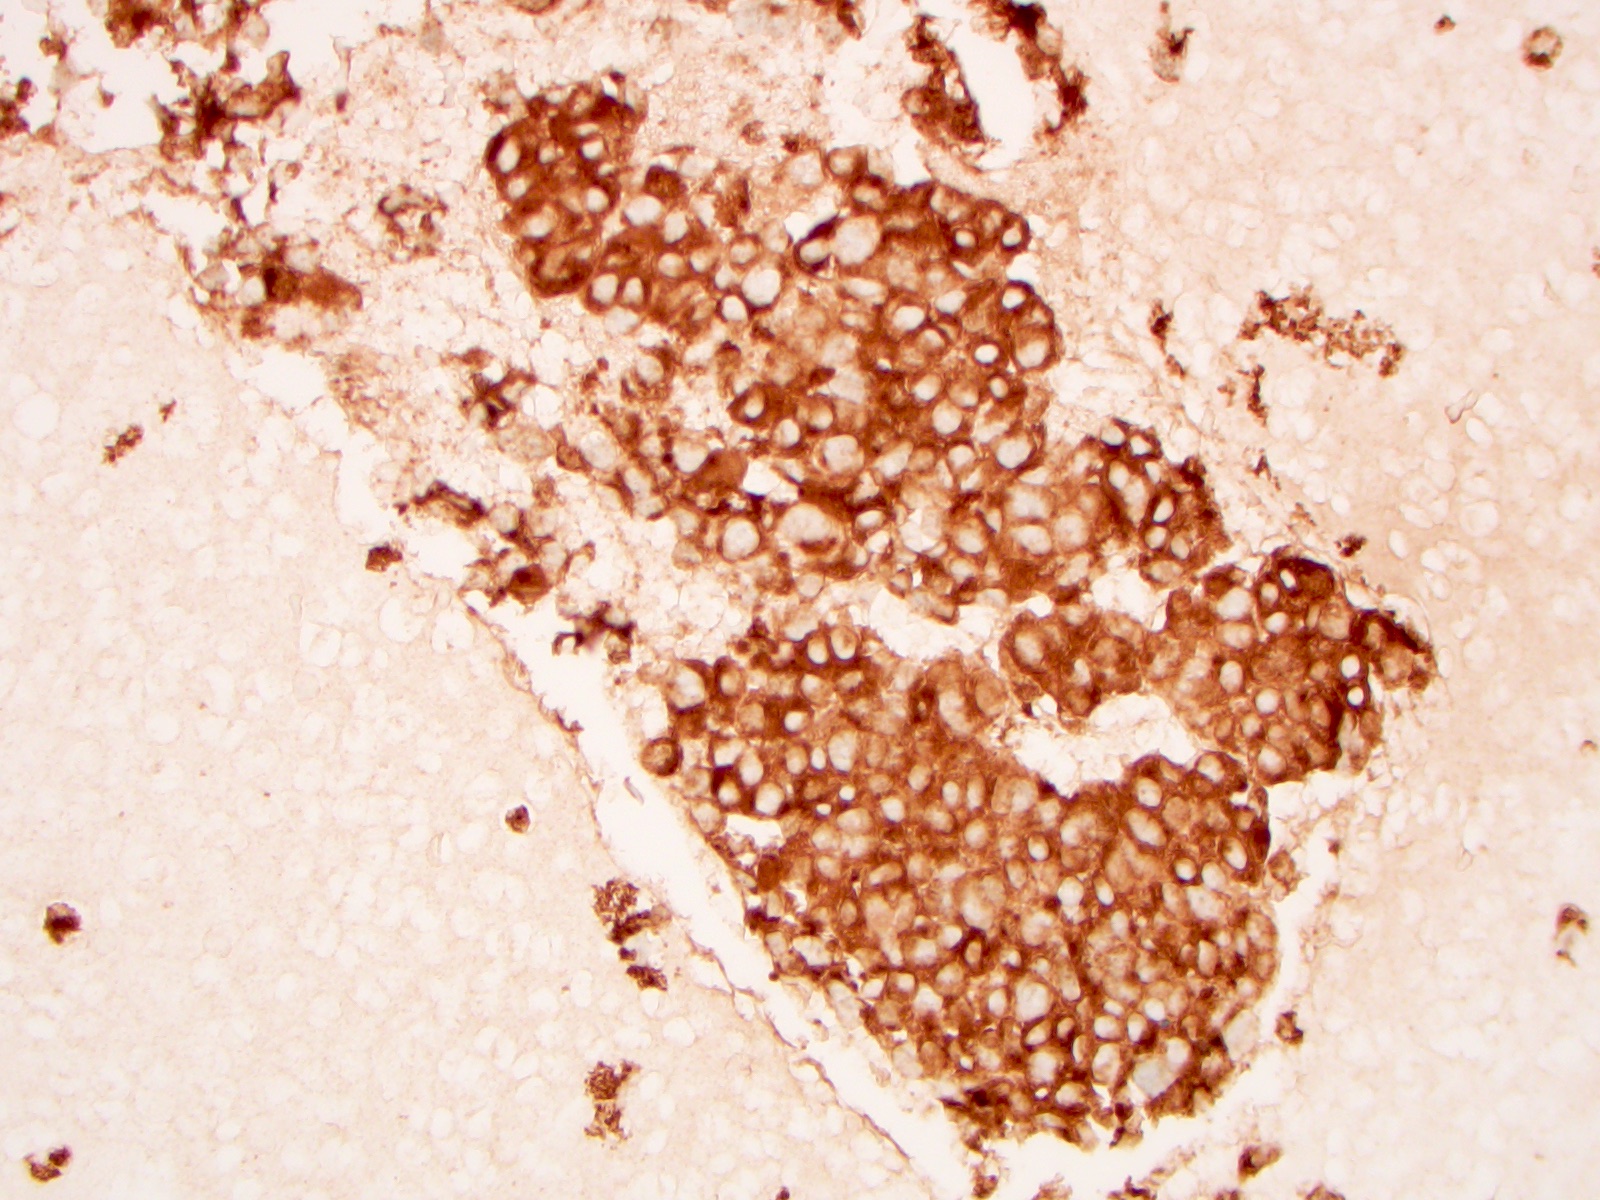

Cytology images

Contributed by Ayana Suzuki, C.T. and Shuanzeng Wei, M.D., Ph.D.

Cytology description

- Cellular specimen with round, ovoid, plasmacytoid or spindle cells singly or in small cluster; cells have abundant cytoplasm and eccentric nuclei; chromatin has salt and pepper appearance

- May have pink azurophilic granules and intranuclear pseudoinclusions; amyloid present occasionally (Am J Clin Pathol 1984;82:552)

- Paraganglioma-like variant:

- Predominantly ovoid to spindled epithelial cells in cohesive three dimensional clusters with sharp margins, rare isolated individual cells, no background colloid or amyloid

- Tumor cells have inconspicuous cytoplasm, significant nuclear atypia with occasional bizarre or binucleated cells, coarse and granular nuclear chromatin with occasional grooves and intranuclear inclusions (Cytopathology 2009;20:188)